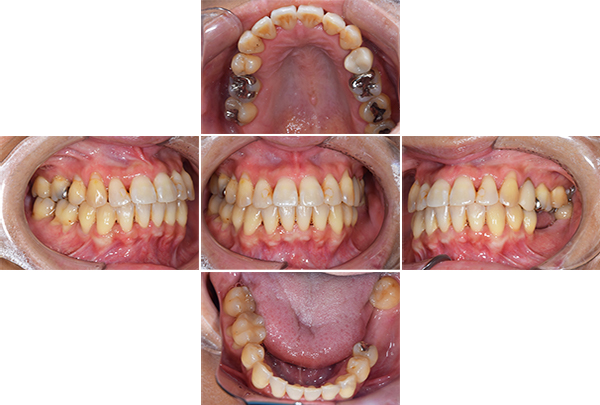

インプラントの症例| 年齢 | 50代女性 |

|---|---|

| 主訴 | 左上の歯ぐきが腫れた |

| 治療期間 | 4年 |

| 費用 | インプラント 1,017,500円(税込) 矯正 880,000円(税込) 虫歯治療 インレー ハイブリッド3本 132,000円(税込) シルバー3本 約6,000円(保険治療のため変動あり) |

1. 歯ぐきのはれの原因である歯周病の治療

2. 虫歯の治療

3. 歯列不正のため、ブラッシングが難しい、かみ合わせの是正のため矯正

4. 矯正終了後インプラント

5. メンテナンス

【担当医師所見】

患者様の初診時レントゲン写真

咬合平面の整頓の必要性 有

交叉咬合、オーバージェットの是正

歯周病の治療の必要性

ブラッシング方法の教授

左右上下合わせて4本の抜歯を行った

①前歯もキレイに並んできました

②上の歯が外側になり、交叉咬合がなくなりました

③左上の出ていた歯を元の位置までもどしています